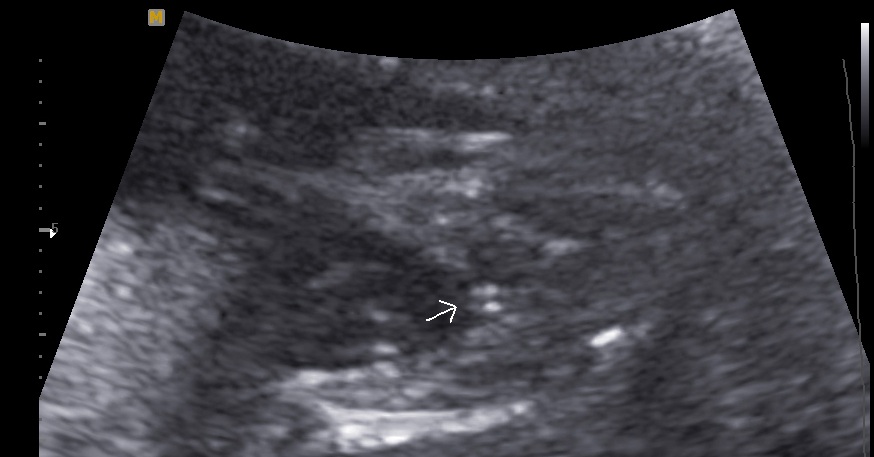

Can anyone take a guess for me the tech said she wasnt sure. She didn't even hint one way or the other just stated we would try again at my next ultrasound on March 11th.

Looks girly!

I think girl! The picture isn't the best quality though.

Girly 'hamburger', congrats!